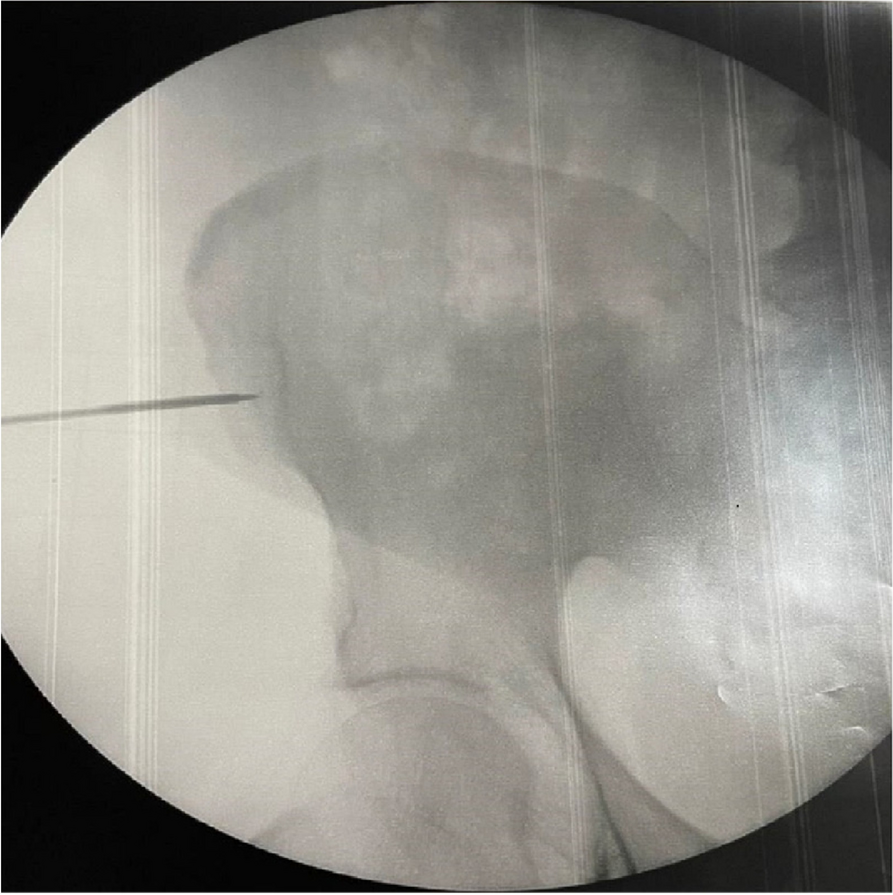

For the past year we have faced a case of anastomotic leakage post esophageal resection, treated through the application of an endoprosthesis esophageal in a patient affected by L. Pneumophila.

The main problem for the anesthetist during this procedure is identifying the most inadequate perioperative management.

In this specific case, the patient, affected by L. Pneumophila, presented a PO2/FiO2 ratio between 100mmHg and 200mmHg, giving rise to a moderate ARDS panel according to Berlin Criteria (Image 1).

For this reason, we decided to use a non-invasive periprocedural ventilation mode, specifically the High Flow Nasal Cannula (HFNC), to reduce the risk of postoperative pulmonary complications due to invasive ventilation through endotracheal intubation (ETI).

Image 1 (abstract A9).

See text for description